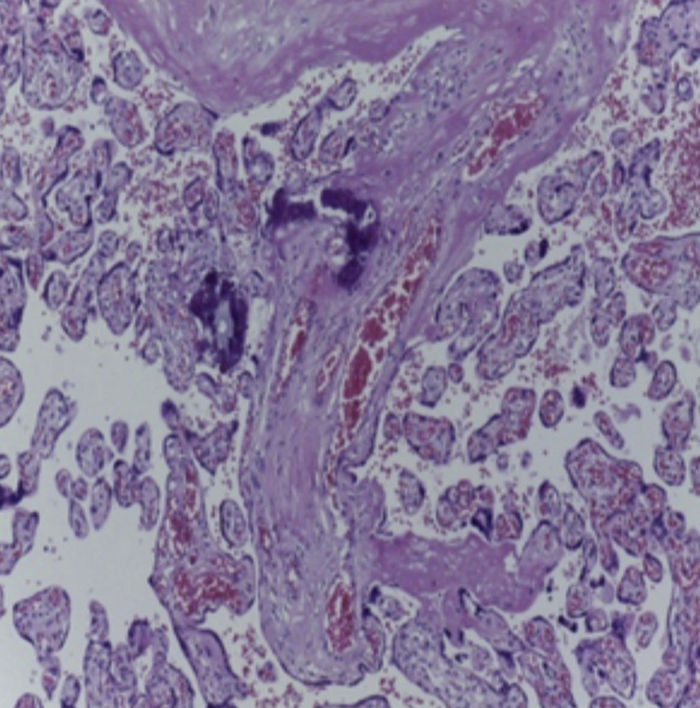

Se observa una pieza quirúrgica que corresponde al lóbulo superior del pulmón izquierdo. Pesó 80 g y presentaba una pleura opaca, despulida y congestiva. A los cortes seriados, se observaron numerosos quistes con un diámetro promedio entre 2 y 5 cm. Entre los quistes había áreas de parénquima pulmonar con congestión importante. Existe un quiste de mayor tamaño, con diámetro de 6 cm, cuya superficie interna es brillante y trabeculada (Figura 3). Otros quistes más pequeños estaban separados por tabiques de tejido conectivo, lo que se corroboró mediante la histología. La malformación estaba constituida por numerosos quistes revestidos por epitelio columnar y epitelio cilíndrico ciliado, que alternaban con algunas células mucosas. Estas células mucosas recuerdan las glándulas intestinales, mucoproductoras; entre estas se observaron tabiques de tejido fibroconectivo con algunas células comprimidas. Entre los quistes revestidos por este epitelio vemos, además, la presencia de músculo liso (Figura 4).

Figura 4 Quistes revestidos por células columnares mucoproductoras y presencia de músculo liso (HE 40X).